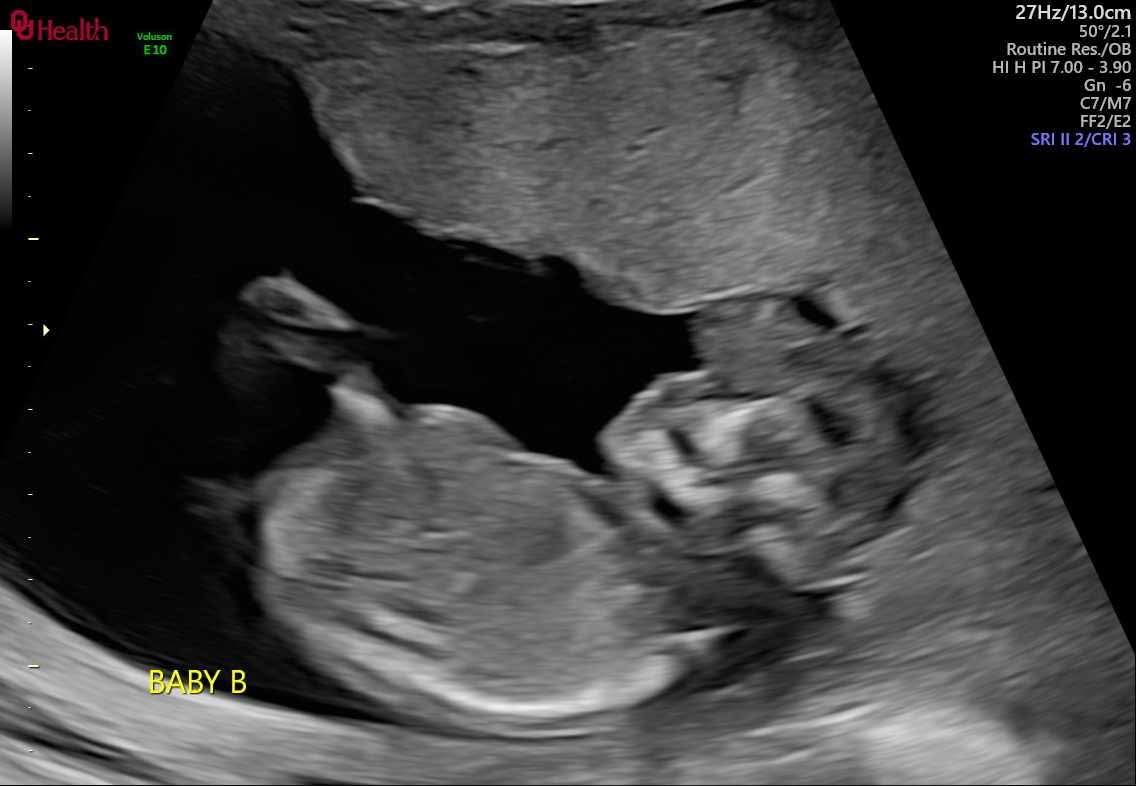

On Wednesday, July 9th 2025 my sister Carmen was rushed into the operating room due to heavy bleeding though she was already being monitored for it for weeks , they had diagnosed her with placenta previa with accreta with this pregnancy. The twins are considered monozygotic twins( high risk) because they shared the same placenta but different sac. Around 5:13am I received a texted message that she had delivered her babies and had received a total of 4 blood transfusions due to the large amount of blood loss which resulted in needing a full hysterectomy.. Baby A has a hear condition called hypoplastic left heart syndrome and will need multiple operations in the future ; however they were born at just 28weeks gestation making it difficult for those surgeries. Baby B had Acrania , polyhydraminas and passed away 1 hour after being born.. he was held and loved deerly by dad and family members but unfortunately my sister was not able to hold him while he was alive. We are asking for prayers, and any help for medical expenses for my sister and funeral expenses for baby Luis Ojeda. Prayers are highly appreciated especially for baby A , Michael Jr Ojeda to receive healing in Jesus name! My sister Carmen and Michael appreciate it very much! Thank you so much for any help with lots of love ❤️